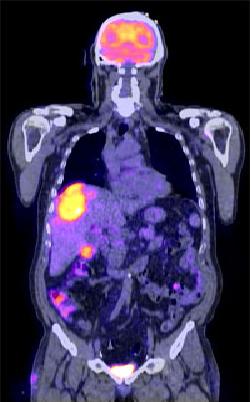

Complementando CT y PET

(ID 2013)

PET y SPECT

(ID 2011)

Radiofarmaco

(ID 2012)